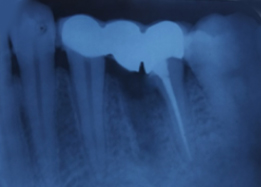

Immediate Post-Surgical IOPAR

Hemisectomy

Radiograph with Prosthesis (8 Months)

Powered By - www.calcuttayellowpages.com